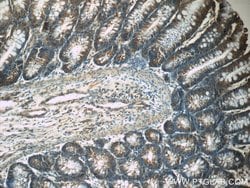

| Immunohistochemistry (Paraffin), Western Blot | |